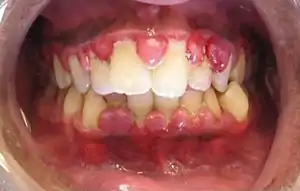

| A severe case of gingivitis | |